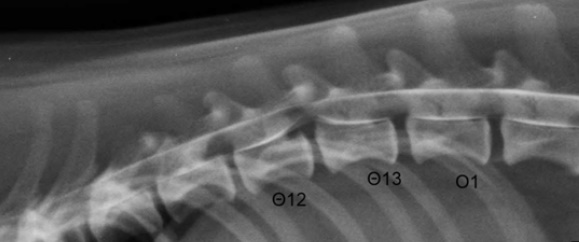

Στις απλές ακτινογραφίες μπορεί να απεικονιστούν αλλοιώσεις, που ενδέχεται να είναι ενδεικτικές δισκοκήλης αλλά δεν αποτελούν κριτήριο για την οριστική διάγνωση. Τέτοια απεικονιστικά ευρήματα είναι η αποτιτάνωση ενός ή περισσοτέρων μεσοσπονδύλιων δίσκων, η στένωση ή το σφηνοειδές σχήμα ενός μεσοσπονδύλιου διαστήματος, η παρουσία ασβεστοποιημένου υλικού του πηκτοειδή πυρήνα στην περιοχή του μεσοσπονδύλιου τρήματος και η στένωση του μεσοσπονδύλιου τρήματος.

Μυελογραφία στη θωρακοσφυϊκή μοίρα της σπονδυλικής στήλης. Απεικονίζεται εξωσκληρίδια συμπίεση του νωτιαίου μυελού, που προκαλείται από την πρόπτωση μεσοσπονδύλιου δίσκου. Η προβολή του δίσκου απεικονίζεται ως λέπτυνση και προς τα άνω μετατόπιση της κοιλιακής ταινίας του σκιαγραφικού με ταυτόχρονη λέπτυνση ραχιαίας ταινίας στο μεσοσπονδύλιο διάστημα Θ12-Θ13. Μερικές φορές, στην οξεία θωρακοσφυϊκή δισκοκήλη τύπου Ι προκαλείται οίδημα στη πάσχουσα περιοχή του νωτιαίου μυελού, που εμποδίζει τη δίοδο της σκιαγραφικής ουσίας στον υπαραχνοειδή χώρο. Αυτό έχει ως συνέπεια την αδυναμία εντόπισης του πάσχοντος μεσοσπονδυλίου διαστήματος.